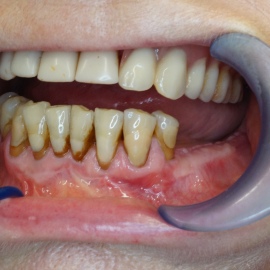

Przedtrzonowce często należą do okolicy estetycznej należy więc zwrócić wzmożona uwagę na poprawną anatomię tkanek kości i dziąsła. Po utracie zęba 25 pacjentka kilka lat chodziła bez jego uzupełnienia, doszło do przesunięcia się zęba 26. U tej pacjentki przed laty był wykonany most jednobrzeżny na czwórce, dość szybko doszło jednak do przeciążenia zęba filarowego, zaniku kości wyrostka i wreszcie pęknięcia korzenia zęba filarowego mostu. Po ekstrakcji i wygojeniu kości stwierdzono ubytek kości wyrostka przekraczający objętość 50% stanu początkowego. Stąd główny nacisk położono na odbudowę tkanek. Uzyskano zadowalający wynik anatomiczny.

Pacjentka lat 41, odbudowa protetyczna zębów 24, 25 na implantach - korony porcelanowe na metalu. Po stronie prawej zdjęto most 13 - 16, poprawiono warunki kostne wyrostka zębodołowego i wykonano most na implantach od czwórki do szóstki, oraz nacementowano pojedynczą koronę na kła.

Pacjentka lat 50. Most od zęba 24 do zęba 27. Pękł korzeń zęba filarowego 24. Po ekstrakcji wykonano zabieg odbudowy kości wyrostka zębodołowego i podniesiono zatokę. Następnie po skorygowaniu kształtu i objętości dziąsła przytwierdzonego wykonano pojedyńcze korony na implantach 24, 26, oraz most 13-17